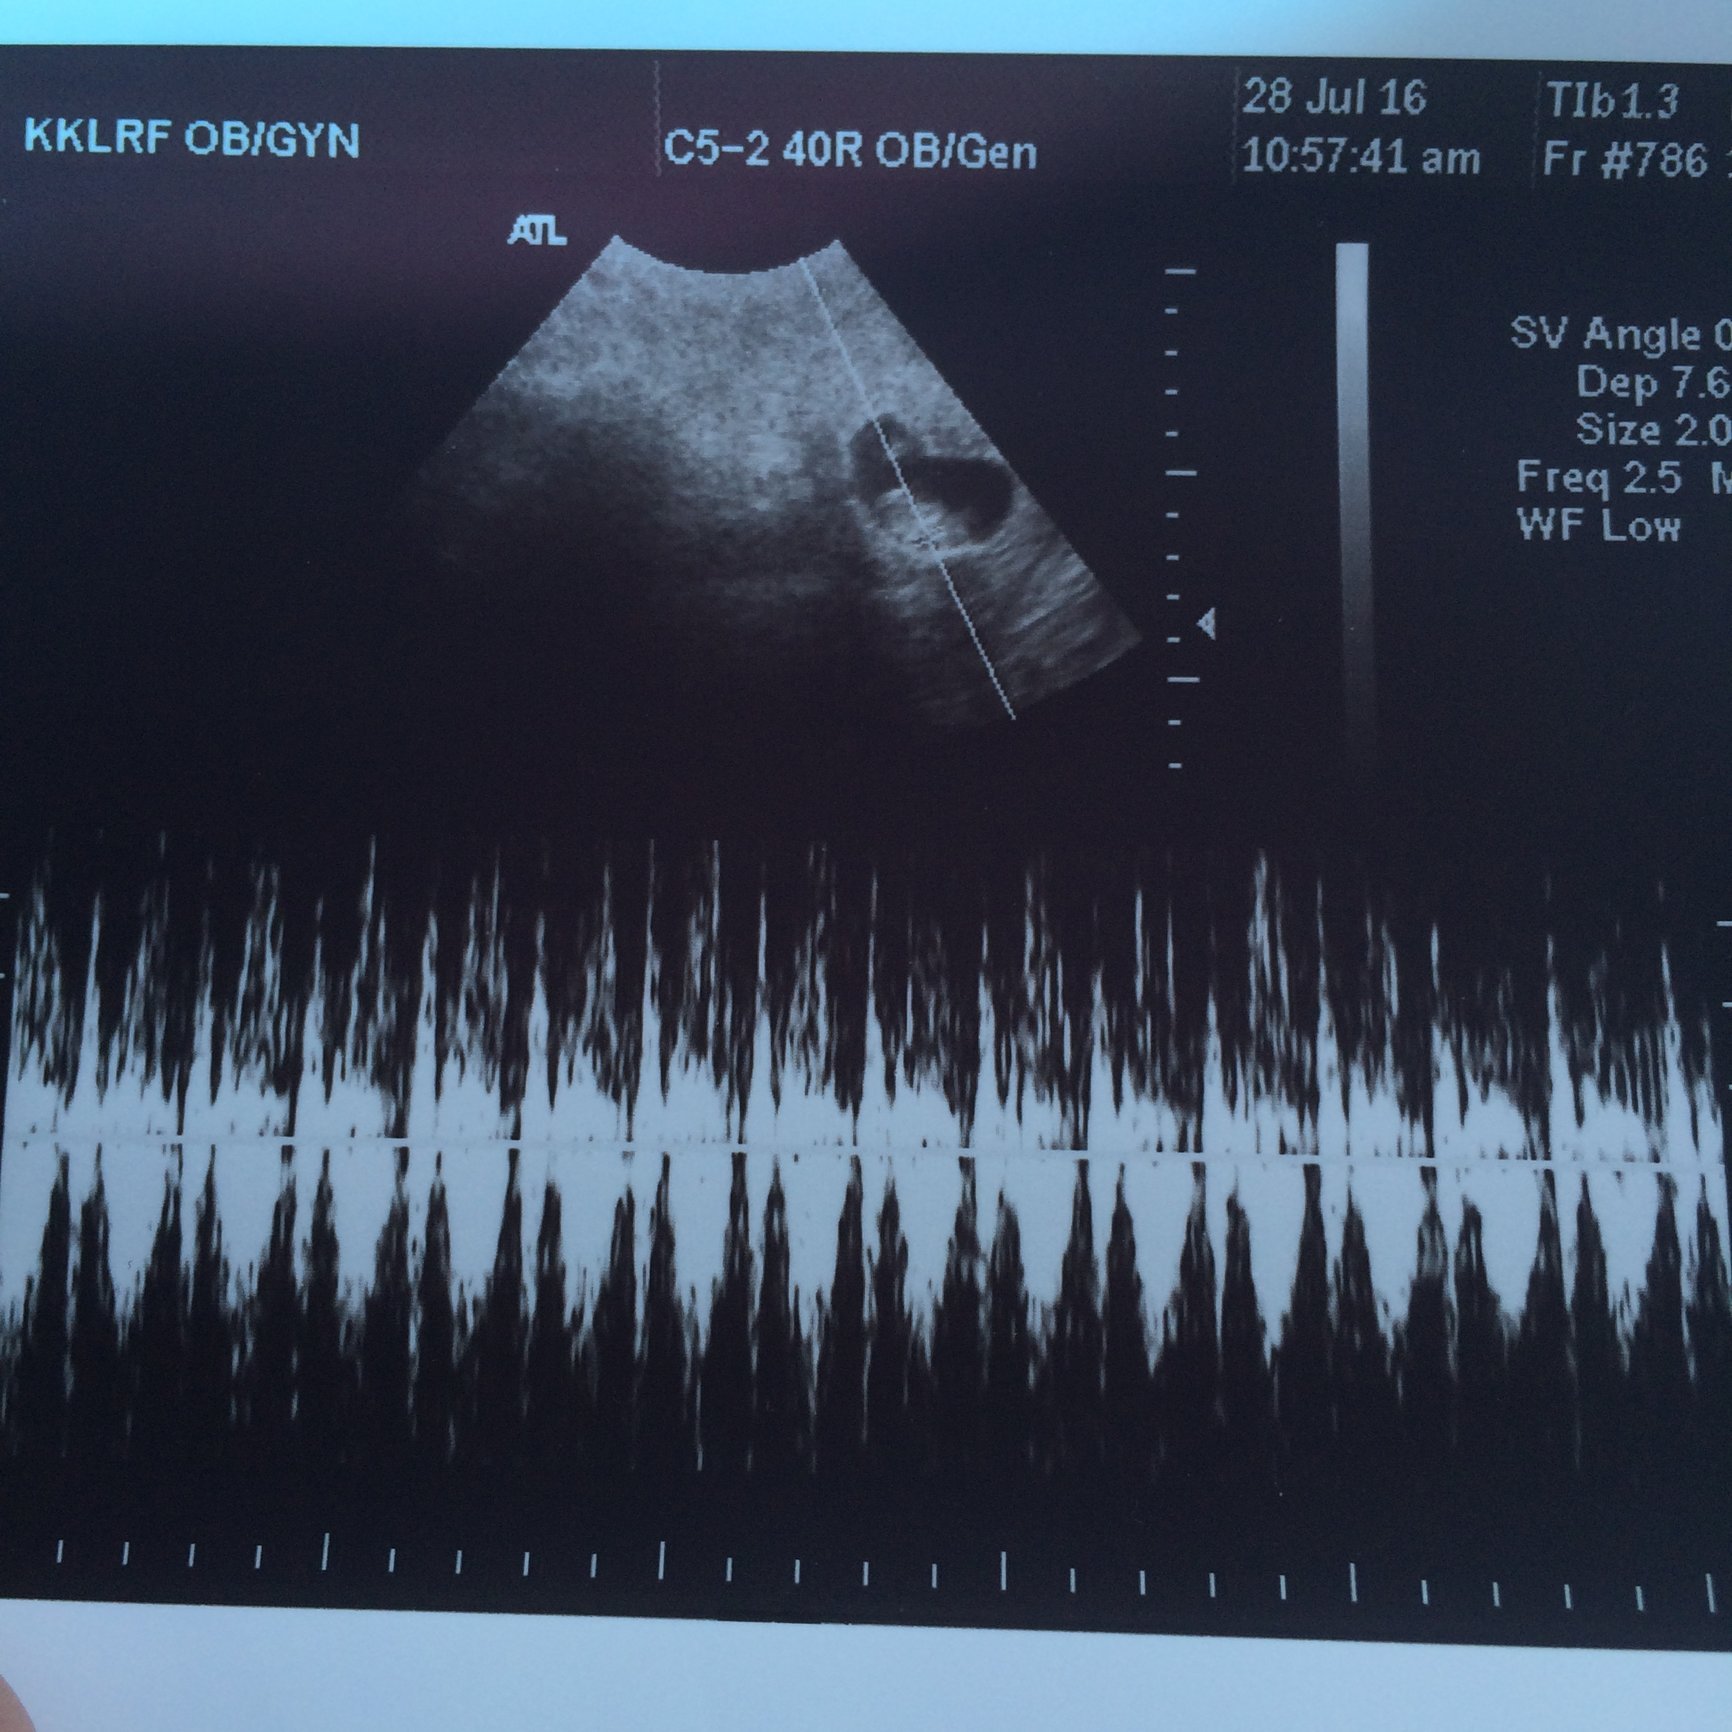

update: since I get to go to the doctor every 1-2 weeks, this is from last Friday.

this is from the high risk obgyn with the better ultrasound machine. good news. she thinks they are monodi but will confirm again in a few weeks

although she is measuring them to be smaller than LMP. by 5-7 days.. due date still in march, ill ask my regular obgyn what she thinks this Friday .

2 little nuggets. good heart rates

147 and 153